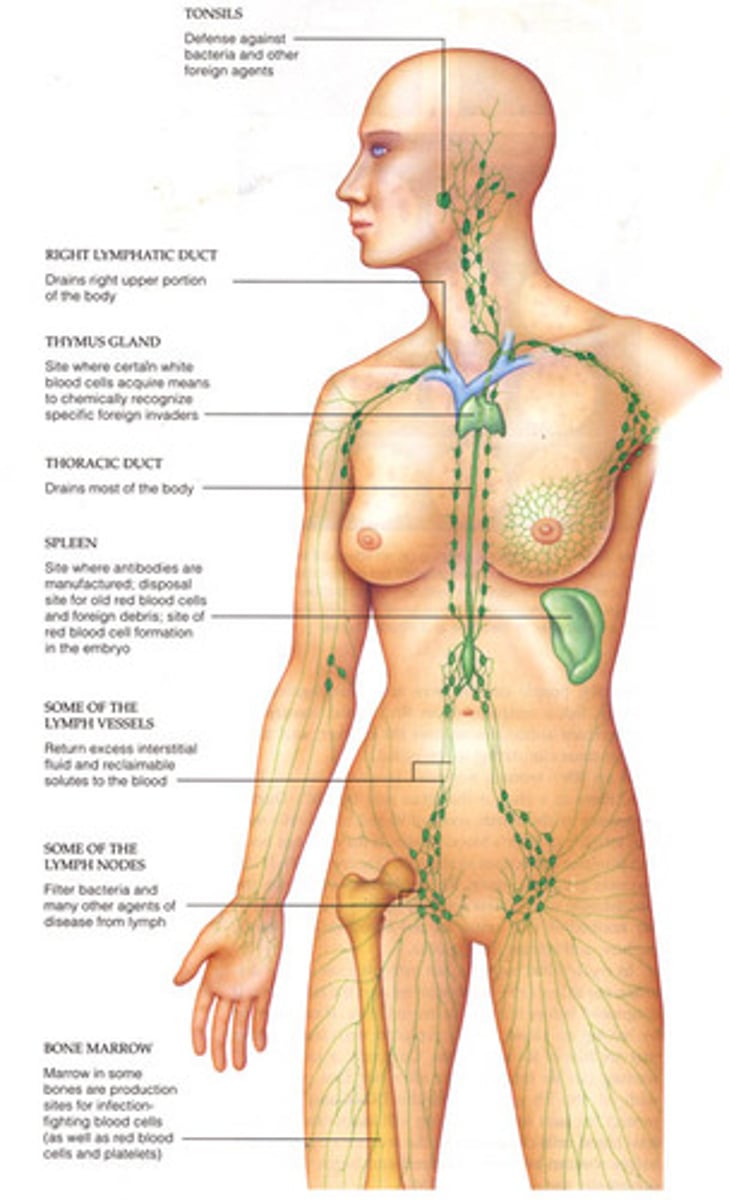

What is the lymphatic system?

Consists of lymph nodes and lymph vessels that carry lymph (a clear fluid right in antibodies). The spleen, thymus, and the tonsils are made of lymphoid tissue. It supports the immune system by housing and transporting white blood cells to and from lymph nodes. This system also returns fluid that has leaked from the cardiovascular system back into the blood vessels.